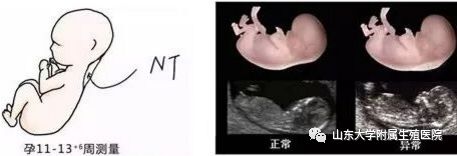

2. NT究竟代表了什么?

NT,是早孕期超声观察到于胎儿颈后的皮下积液,在孕11周至孕13+6周清晰可见,通常于中孕期消退。NT是排查胎儿是否畸形的重要检查手段之一,那么NT能检查出所有的胎儿异常或胎儿畸形吗?答案:NO!NT增厚越明显,发生胎儿结构异常或染色体异常的概率越大,但是,约80%-90%NT异常是胎儿一过性病变,有转归正常的可能。